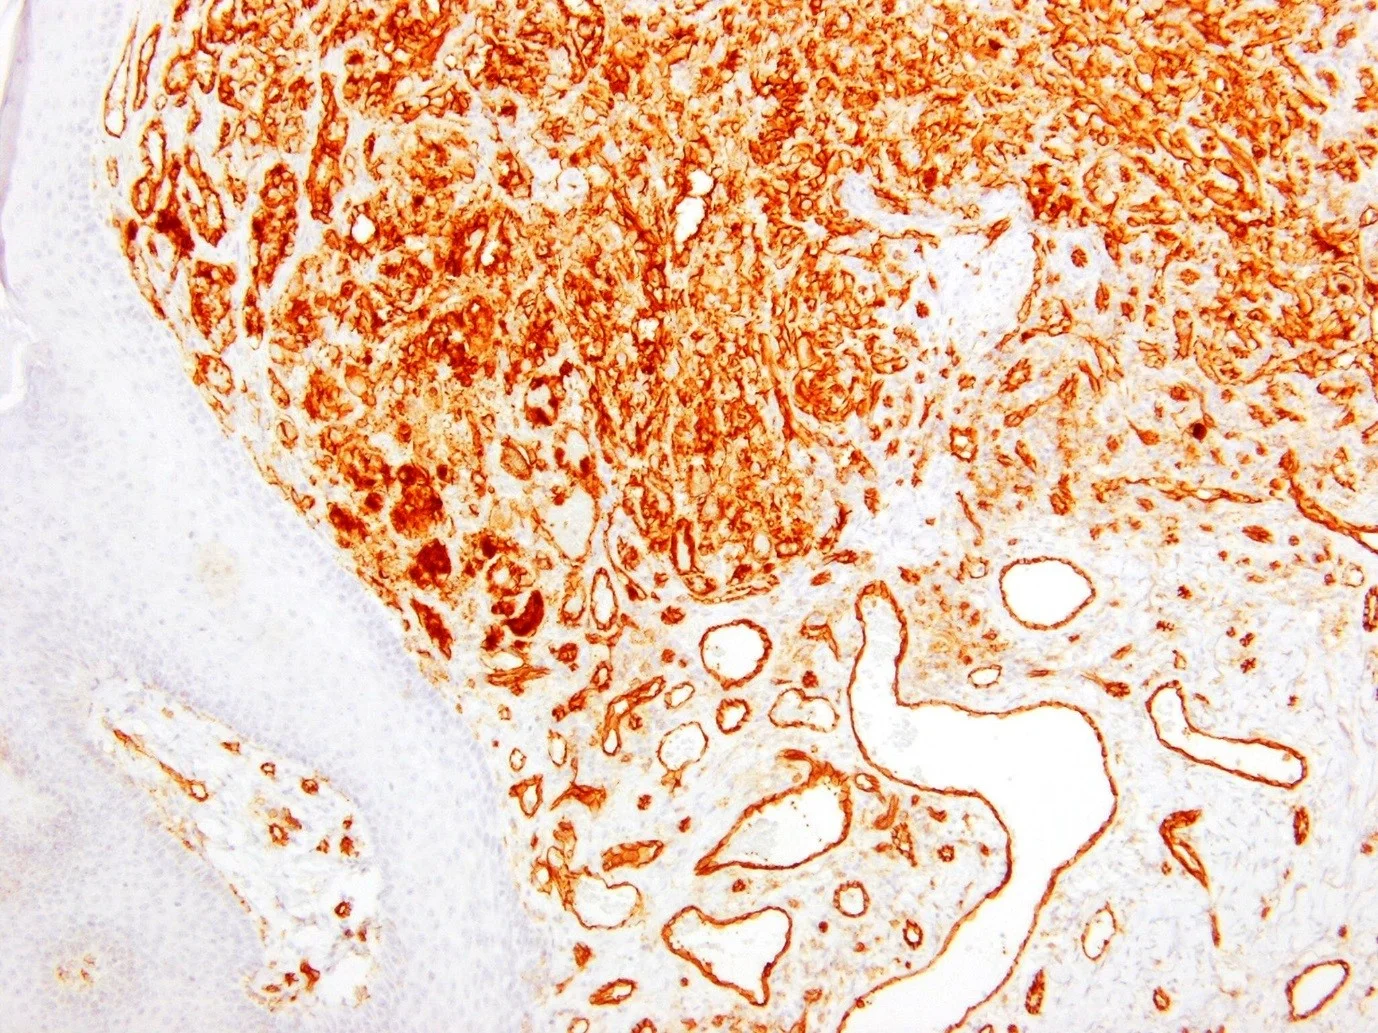

Clinical history: Male age 72. Tumour excised from the abdomen. The dermatologist suggested melanoma, BCC or a metastasis.

CD31